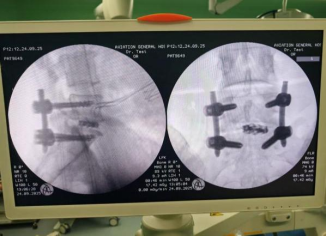

机器人辅助下椎弓根钉导丝和减压套管位置良好

术中见椎弓根钉位置良好